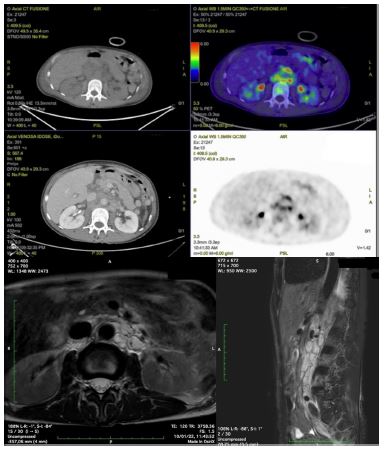

Hypoxemic respiratory failure developed on day + 8, requiring ICU admission and non-invasive respiratory support and thoracentesis. Empiric antibiotic therapy with piperacillin/tazobactam and vancomycin again did not result in clinical improvement. Underlying lymphoma was hypothesized and TC/PET was performed on day + 12. Increased uptake (max SUVs 7.34) in the retroperitoneal area and perivisceral adipose tissue was found; cervical, mediastinal and inguinal lymph nodes were also weakly positive (Figure 1).

Figure 1: (a) CT/PET total body showing a retroperitoneal mass with increased uptake (SUVs 7.34) in the periaortic area at L1-L3 level. (b) T2w MRI acquisition in sagittal and axial plane: the detection of T2 high intensity inflammatory tissue around enlarged limphonods (arrow) suggest the possible diagnosis of immune related pathology